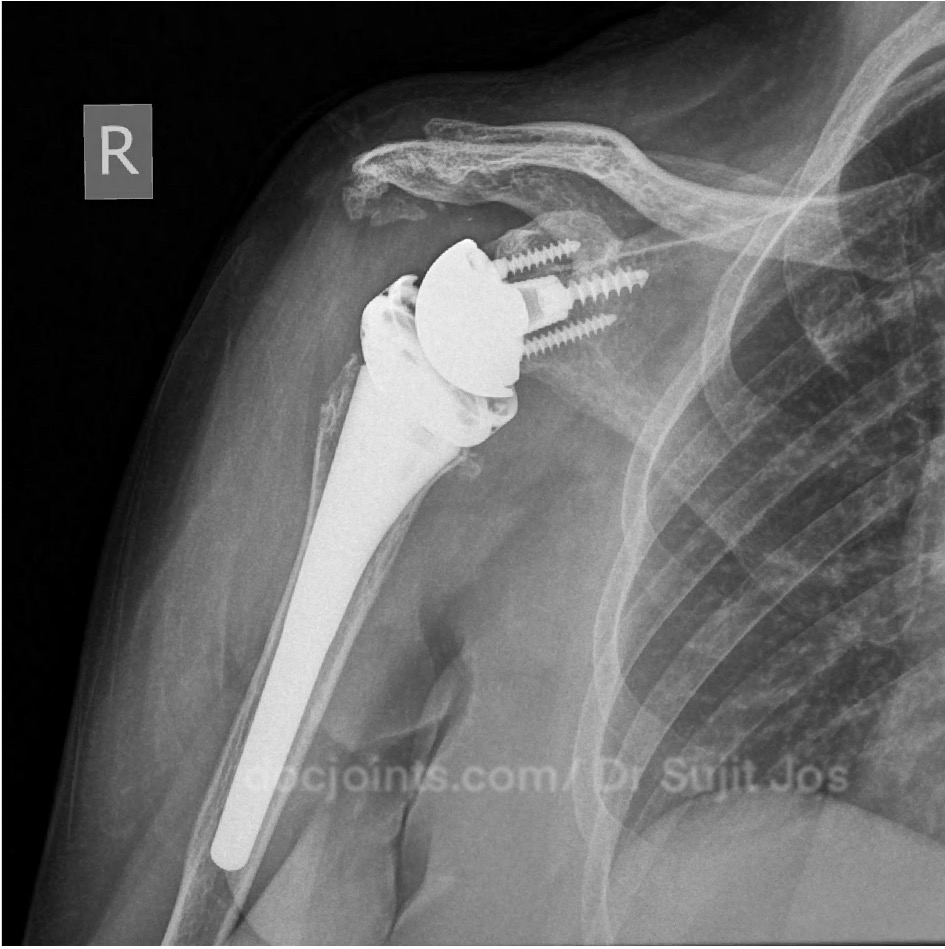

Re Retear of Rotator cuff repair done elsewhere. Failed Rotator Cuff Repair Managed with Reverse Shoulder Arthroplasty

At this stage, we discussed the available options with her. Considering her age, the condition of the joint, and her previous surgeries, we recommended a reverse shoulder replacement — a procedure designed to restore function even when the tendons are no longer working.

The surgery went smoothly.

Today, one year after surgery, she is one of our happiest patients.

She moves her shoulder comfortably. She sleeps peacefully. She lives independently again.